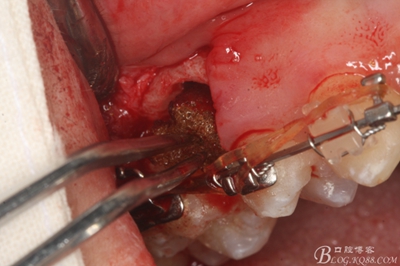

圖15 .微創(chuàng)挺把15牙根縱分成近遠(yuǎn)中兩塊

圖16.微創(chuàng)挺挺松近中根面部分,從16與14之間間隙出來

圖17.血管鉗取出近中部分15牙根